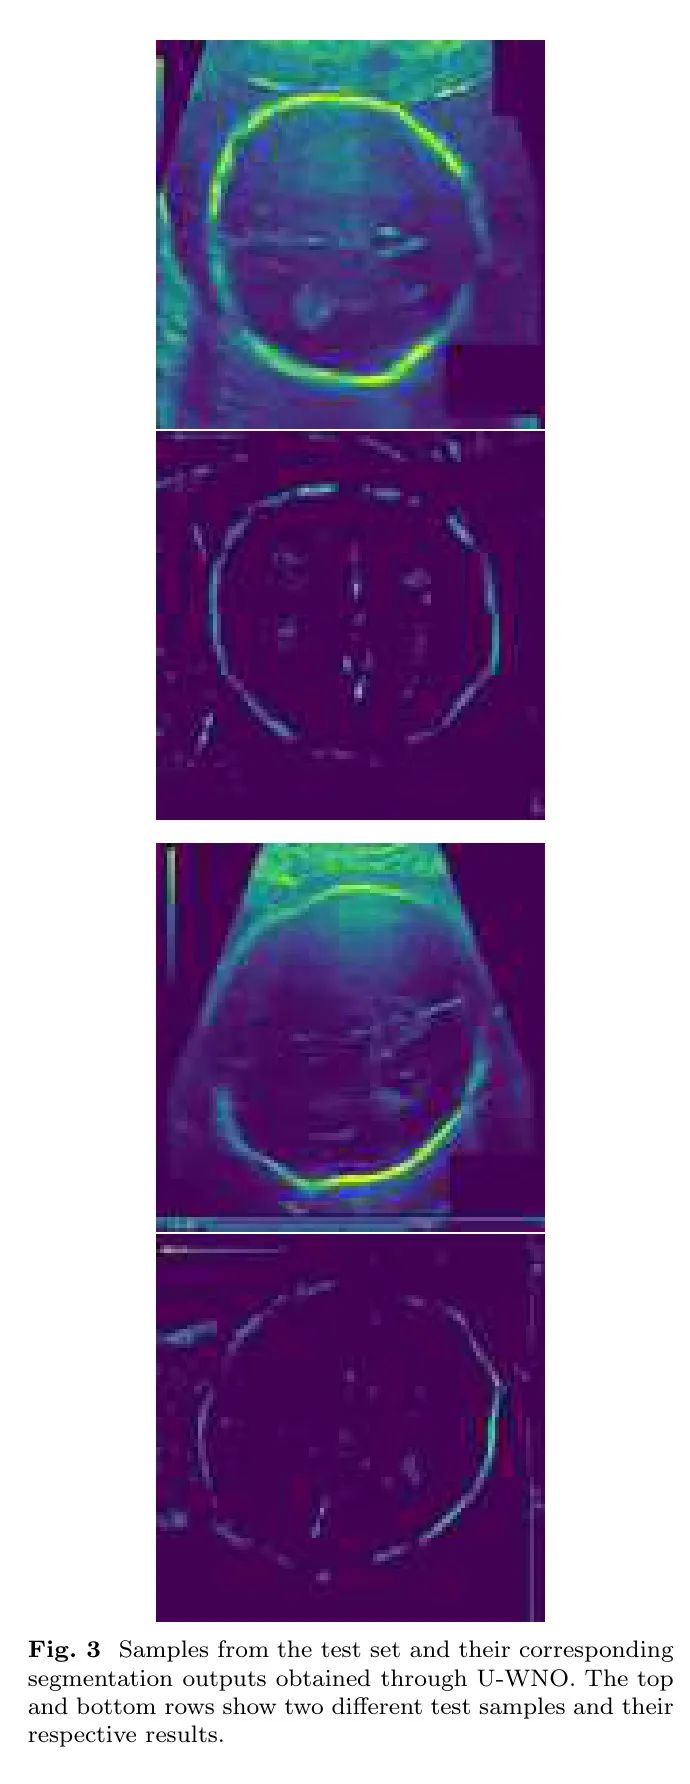

图3展示了在测试集上应用U-WNO后生成的代表性样本。这些可视化结果强调了模型在噪声背景和减小图像尺寸的情况下,能够识别出复杂模式的能力。